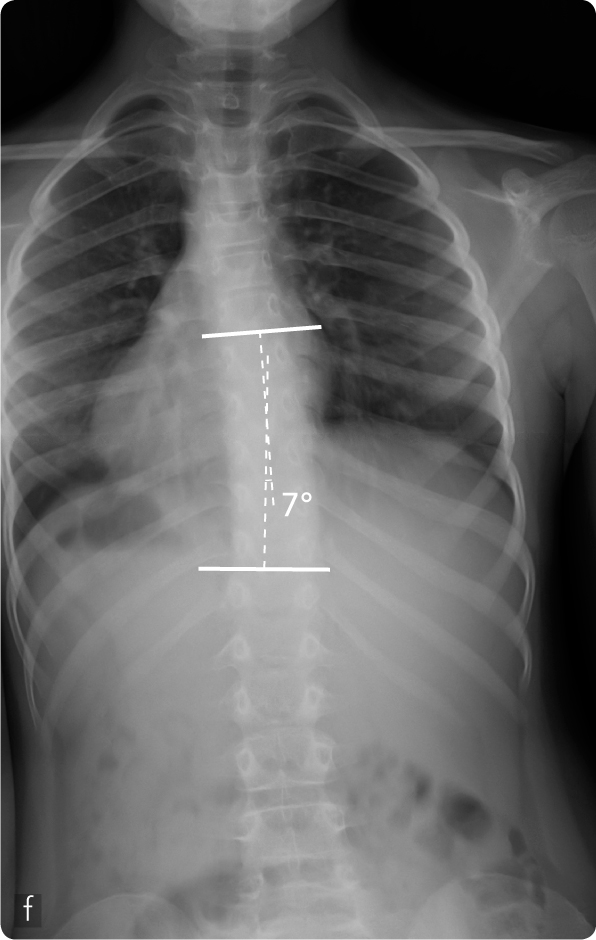

Femmina, 8 anni, scoliosi dorsale destra (a). Asimmetria del profilo delle scapole e dei fianchi (b) ed evidente gibbo dorsale destro (c). Trattamento con busto gessato in deflessione (d). Obiettiva riduzione del gibbo ai controlli successivi in particolare alla flessione anteriore del tronco (e) confermata dal controllo radiografico (f).